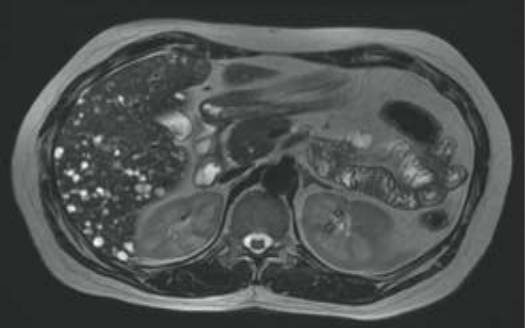

Analise a imagem de ressonância magnética ponderada em T2 e assinale o diagnóstico mais provável: